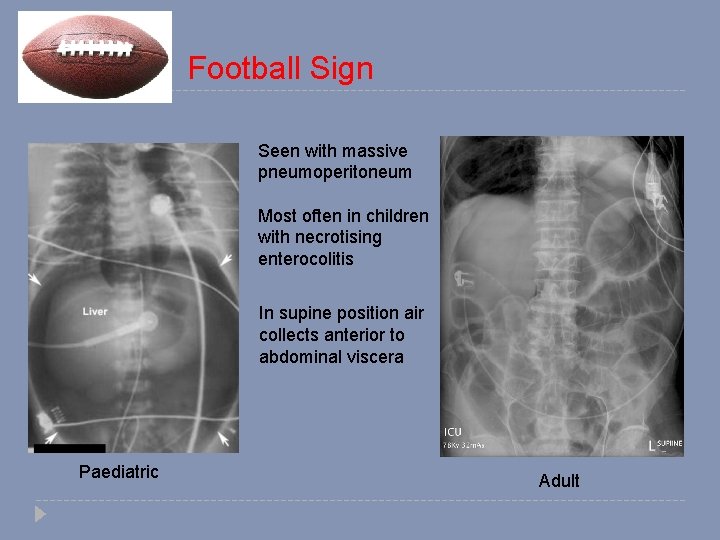

Football Sign Seen with massive pneumoperitoneum Most often in children with necrotising enterocolitis In supine position air collects anterior to abdominal viscera Paediatric Adult